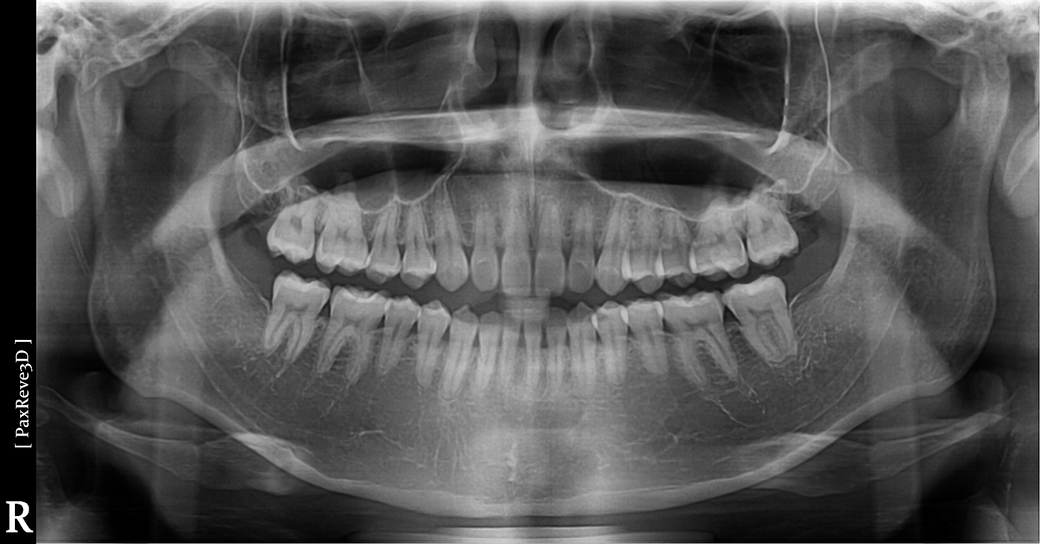

• 1번 째 사진